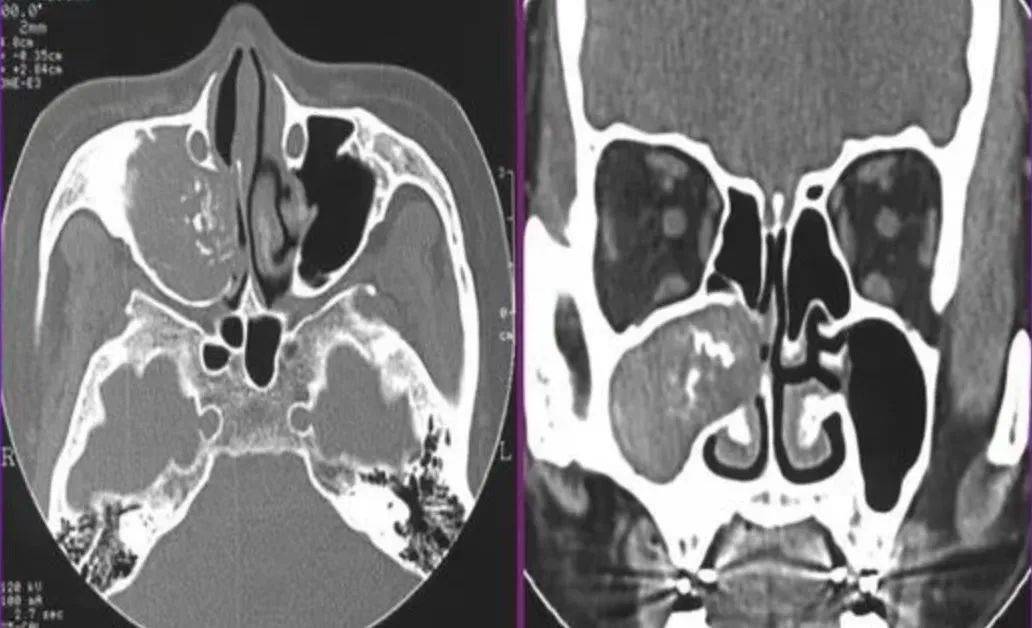

真菌性鼻窦炎影像学诊断